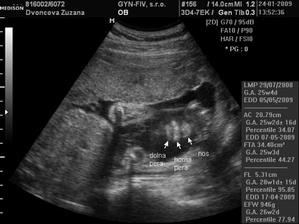

24.1.2009 nám pán doktor prezradil na 3D, že čakáme chlapčeka :o) ....po dlhom rozhodovani sme si povedali, ze to bude maly Nicolas...uz sa velmi tesime, ked pride na svet...caka ho tu cela velka rodina, ktora ho uz teraz velmi lubi :o))